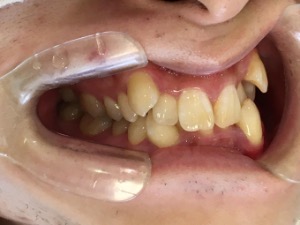

before

after

患者さんの年齢 20代 女性 症状 ガタガタを治したい 治療内容 マウスピース矯正治療 費用 90万(税抜) 治療期間・回数 治療期間2年、通院回数10回 メリット 笑顔が綺麗 デメリット・リスク 期間がかかることがある - マウスピース矯正